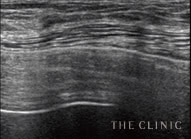

実際のエコー画像

治療前

吸引中

治療後